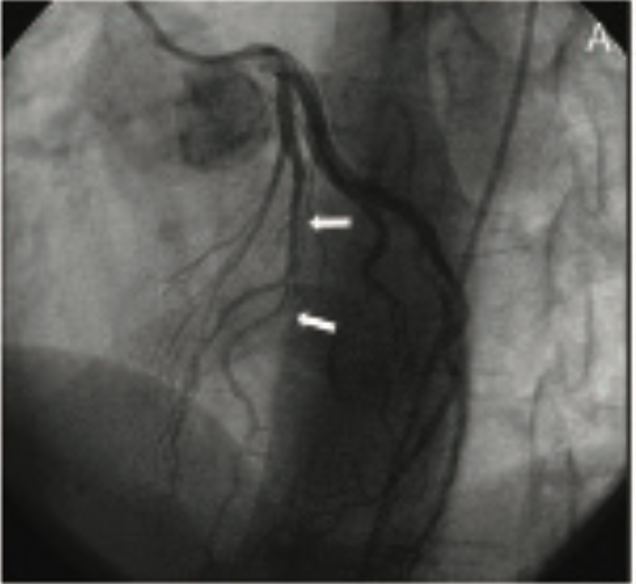

Spontaneous coronary artery dissection (SCAD) is increasingly recognized as a cause of acute coronary syndrome (ACS) and sudden cardiac death, particularly among young women. Although previously estimated to be rare, increasing awareness of heart disease among young women and detection by coronary angiography has increased the recognition of SCAD. SCAD is defined as the spontaneous separation of the coronary vessel wall in the absence of atherosclerosis or iatrogenic trauma. The dissection can involve any of the three layers of the coronary artery wall: the intima, the media, and/or the adventitia. There are two plausible hypotheses regarding the inciting event that leads to the development of SCAD. SCAD can result from an initial intimal tear leading to creation of a false lumen or from primary spontaneous hemorrhage of the vasa vasorum within the vessel wall, leading to formation of an intramural hematoma (IMH). Both mechanisms result in creation of a false lumen and separation of the coronary artery wall, resulting in compromised coronary artery flow through the true lumen.1